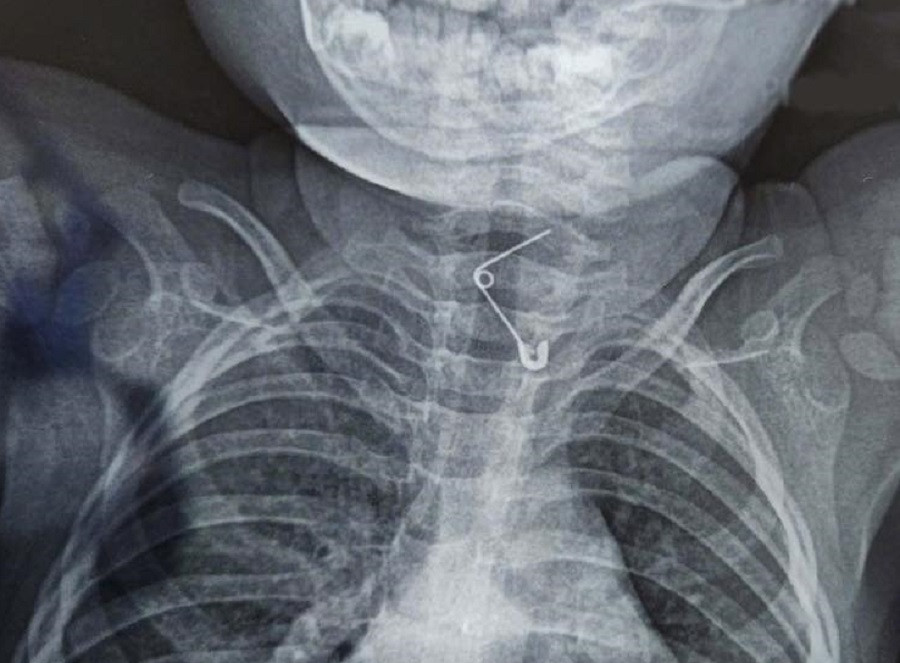

| Bệnh nhi đã bị chiếc kim băng ghim vào thực quản sau khi người lớn cố dùng tay móc dị vật |

Tại Bệnh viện Nhi Đồng 2, qua chẩn đoán hình ảnh, bác sĩ xác định dị vật đang bị kẹt ở thực quản của trẻ. Kết quả nội soi cho thấy, cây kim băng đã bung ra hình chữ L đầu nhọn cắm sâu vào thành thực quản khiến trẻ đối mặt với nguy cơ thủng thực quản, xuất huyết và nhiễm trùng nghiêm trọng.